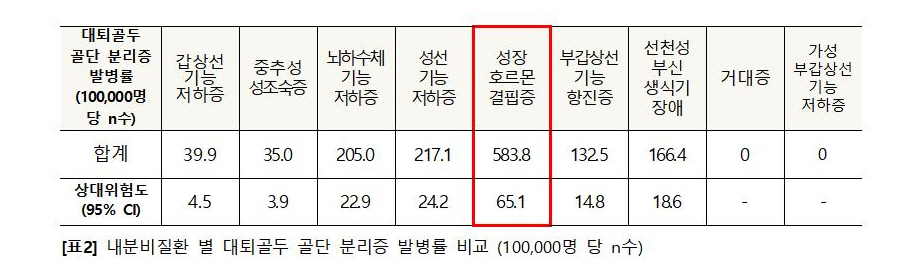

또한 연구팀은 △갑상선 기능 저하증 △중추성 성조숙증 △뇌하수체 기능 저하증 △성선 기능 저하증 △성장호르몬 결핍증 △부갑상선 기능 항진증 △선천성 부신 생식기 장애 △거대증 △가성 부갑상선 기능 저하증 등 각 내분비질환 별 대퇴골두 골단 분리증의 발병 위험을 분석했다. 그 결과, 성장호르몬 결핍증으로 성장호르몬 치료를 받는 환자군에서 대퇴골두 골단 분리증의 발병률이 일반인 대비 약 65배로 가장 높은 것으로 나타났다.

[표2] 내분비질환 별 대퇴골두 골단 분리증 발병률 비교 (100,000명 당 n수)